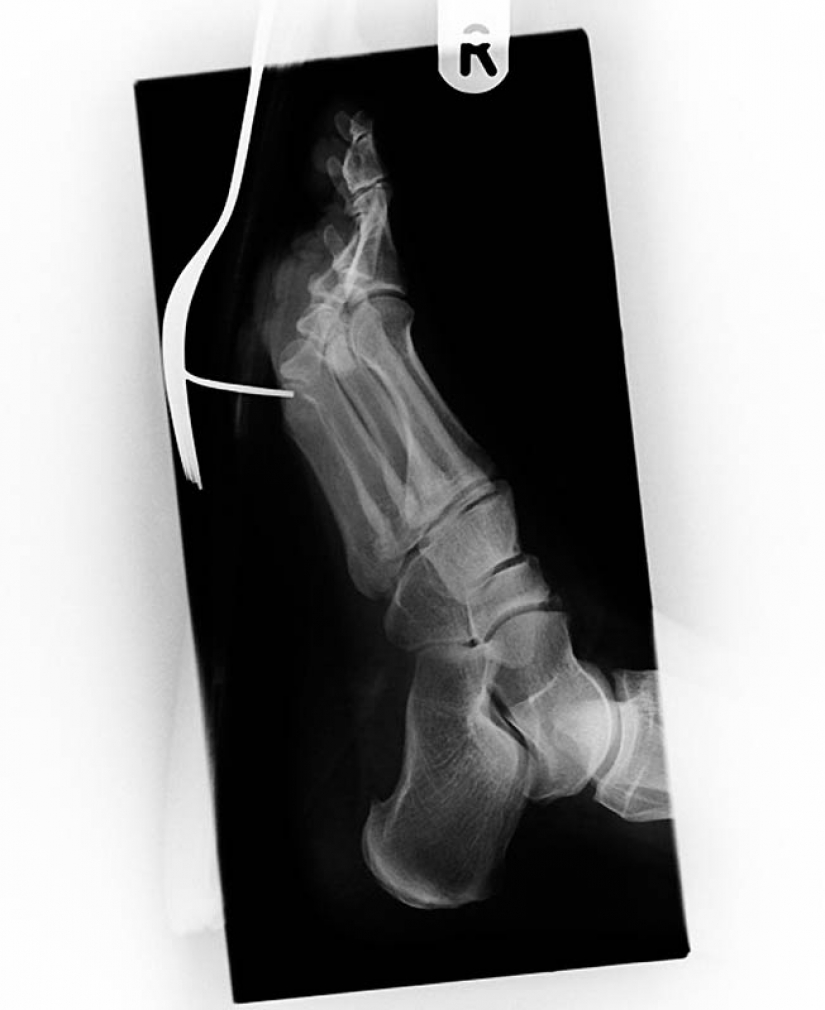

3. Vintage x-ray of the foot soldier of the Anglo-Boer war (1899-1902) with a gunshot wound. The bullet lodged in metatarsal between the thumb and second fingers.